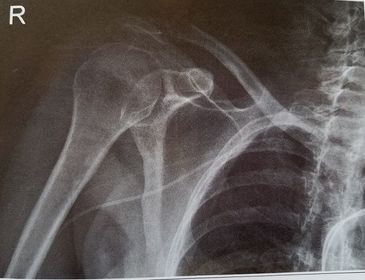

| AP Shoulder internal rotation | the MCP is tilted posteriorly as marked by the superior scapular angle is inferior to the clavicle |

| AP Shoulder | patient is rotated towards the unaffected shoulder: decreased thoracic superimposition over the scapular body |

| AP Shoulder | patient is rotated towards affected side:increased thoracic superimposition over the scapular body |

| AP Shoulder Neutral | ANATOMY: proximal humerus, lateral 2/3 of clavicle, open shoulder joint CRITERIA: humeral epicondyles are 45 degrees to the IR neither tubercle should be seen on the humeral head POSITIONING: CR perpendicular @ 1'' inferior to coracoid process |

| AP Shoulder Internal Rotation | CRITERIA: lesser tubercle in profile medially POSITIONING: CR perpendicular @ 1'' inferior to coracoid process |

| AP Shoulder External Rotation | CRITERIA: greater tubercle in profile laterally POSITIONING: CR perpendicular @ 1'' inferior to coracoid process |